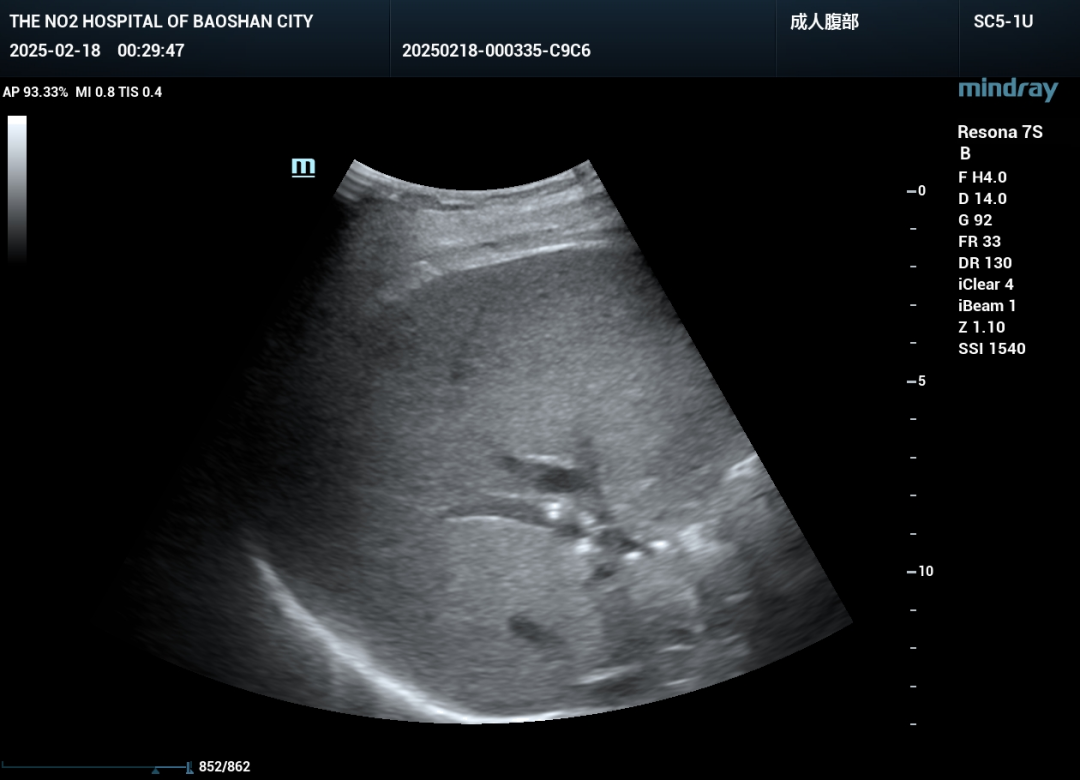

好景不长,在一次复查中发现患者任然存在部分胆管扩张。面对这一状况,超声医学科为患者制定了第二次PTCD手术方案。

第二次手术同样充满挑战,超声医学科团队再次突破重重难关,手术取的成功。回访了解,目前患者病情平稳,后续治疗也在有序进行中。

手术时,患者取仰卧位,这是最利于医生操作的体位。在超声引导下(保山二院超声医学科的超声引导技术非常出色,能清晰展示胆管及周围组织的结构),医生仔细确定穿刺点和穿刺路径,这一步对手术成败和患者安全至关重要。确定位置后,进行局部麻醉,减轻患者术中痛苦。随后,使用穿刺针经皮穿刺进入肝脏,再精准穿刺进入扩张的胆管。成功穿刺胆管后,引入导丝,沿导丝将引流管置入胆管合适位置,最后妥善固定引流管,确保胆汁能顺利引出,手术完成。